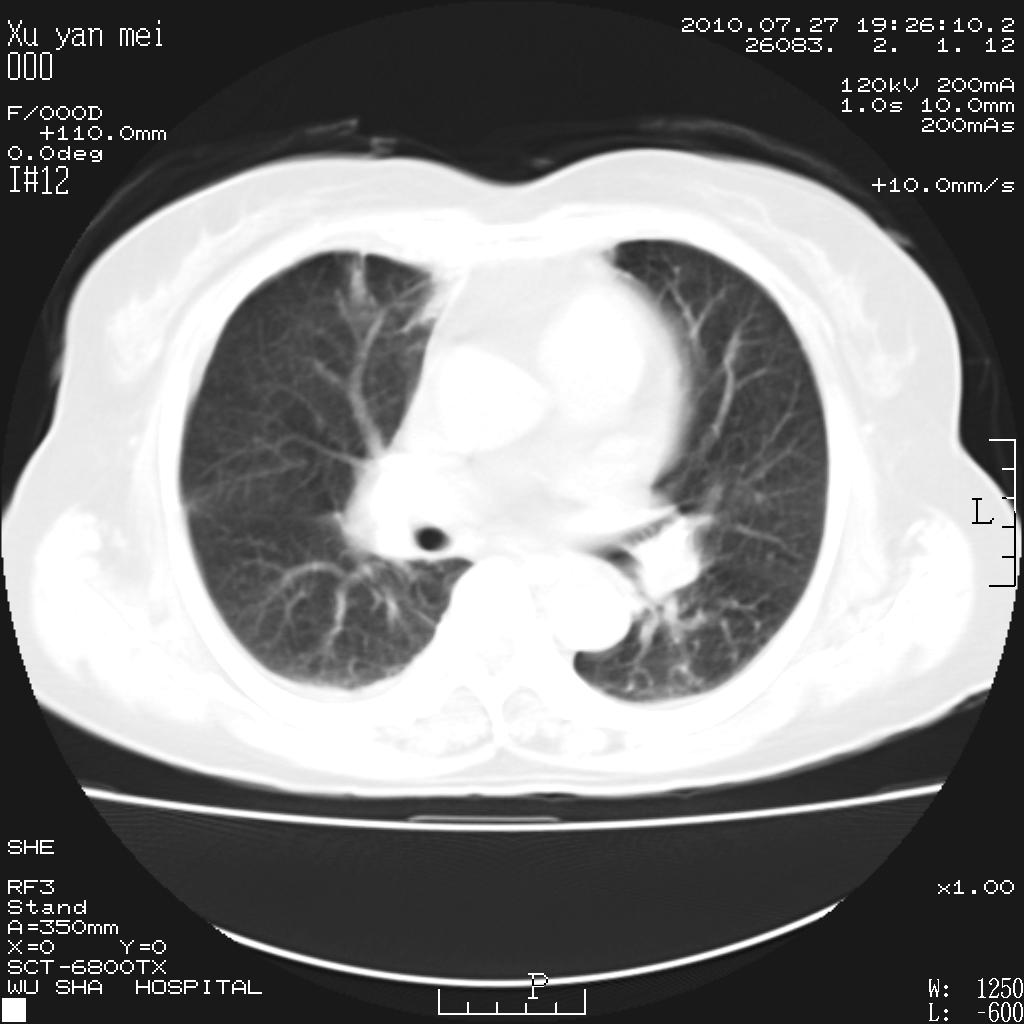

女,60岁,胸痛就诊,右肺结核?炎症?其它?(胸片右侧中上肺野确实看不到什么啊)

1)考虑两肺感染性病变;建议抗炎治疗后复查。2)双侧少量胸腔积液。

1)考虑两肺感染性病变;建议抗炎治疗后复查。2)右侧少量胸腔积液。

双肺炎症可能性大,建议抗炎后复查。右侧胸腔少量积液。双侧胸膜轻度增厚。

考虑两肺感染性病变;不除外肺栓;建议抗炎治疗后复查。